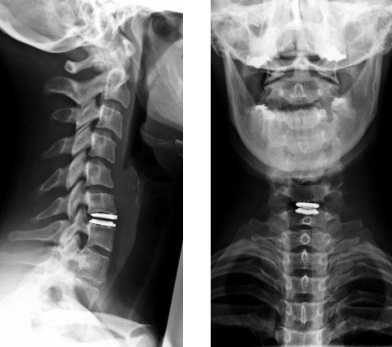

Рентген шейного отдела позвоночника имеет целый ряд особенностей. Выполняться процедура может в нескольких проекциях, а именно:

- прямая задняя;

- прямая задняя через открытый рот - нужна для осмотра 1-3 шейных позвонков;

- боковая;

- косая задняя.

Полную протяженность шейного отдела позвоночника можно увидеть только в положении сбоку. Если же снимок делается в прямой проекции, тень от нижней челюсти будет закрывать первый и второй позвонки. Чтобы получить качественное изображение, потребуется сделать прицельный снимок через открытый рот пациента.

Как правило, назначается процедура рентгена шейного отдела позвоночника в двух проекциях - боковой и прямой. Дополнительно может назначаться косая, если нужно детально рассмотреть межпозвонковые отверстия.

Рентген шейного отдела позвоночника в двух проекциях

Чаще всего процедура выполняется в обычной прямой и боковой проекциях. Как правило, такого исследования достаточно, чтобы оценить состояние позвонков и определить причину жалоб пациента. По получении снимков могут быть назначены дополнительные исследования, которые позволят оценить состояние мягких тканей шеи, либо же будет прописано лечение, если информации окажется достаточно.